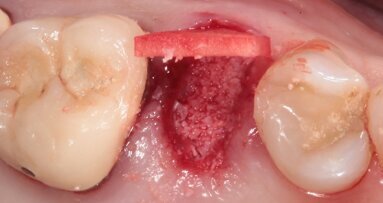

In fase preoperatoria è stato prescritto aerosol (2 volte al giorno per 7 giorni) con beclometasone dipropionato (Clenil 0,8 mg/2 ml) e soluzione ipertonica (Libenar 22g/l) a partire da 7 giorni prima dell’intervento e antibiotico (Amoxicillina 1 g - ogni 12 ore a partire dal giorno precedente l’intervento per 6 giorni). È stato eseguito il rialzo di seno mascellare del secondo quadrante per via laterale abbinato a una contestuale tecnica di GBR/Guided Bone Regeneration (Figg. 4-6). Come sostituto osseo è stato utilizzato lo xenoinnesto bovino Re-Bone® (Ubgen, Padova, Italy) da 1 g con granuli cortico-spongiosi 0,25-1 mm (Figg. 7, 8, 11). Questa metodica è stata abbinata a Shelter ® membrana in pericardio bovino (Ubgen, Padova, Italy) fissata poi con appositi pins ritentivi (Figg. 12, 14, 15). Terminata la tecnica di GBR, sono stati suturati i lembi (Vicryl, 4/0, Johnson & Johnson Int.) (Fig. 16).

Per la fase post-operatoria sono stati prescritti un analgesico da prendere al bisogno (Paracetamolo 500 mg), cortisone (Bentelan 1 mg, 4 compresse il primo giorno e a scalare i giorni successivi fino ad 1 il quarto giorno) e clorexidina 0.2% e sono state fornite istruzioni complete all’igiene orale. Dopo 7 giorni dall’intervento è stato prescritto nuovamente aerosol (beclometasone dipropionato Clenil 0,8 mg/2 ml) e soluzione ipertonica (Libenar 22g/l per 7 giorni). La sutura è stata rimossa dopo 10 giorni. A distanza di 7 mesi dalla procedura rigenerativa è stato attuato un secondo timing chirurgico per posizionare gli impianti nella sede prestabilita. Eseguita l’anestesia locale sono stati inseriti impianti endossei in posizione 24 (3.2 x 10 mm.) e 26 (4.3 x 10 mm) (JD Evolution Plus - JD Dentalcare, Modena, Italy) (Figg. 17, 18) ed eseguita la radiografia di controllo postoperatoria. La rimozione delle suture è avvenuta dopo 10 giorni.